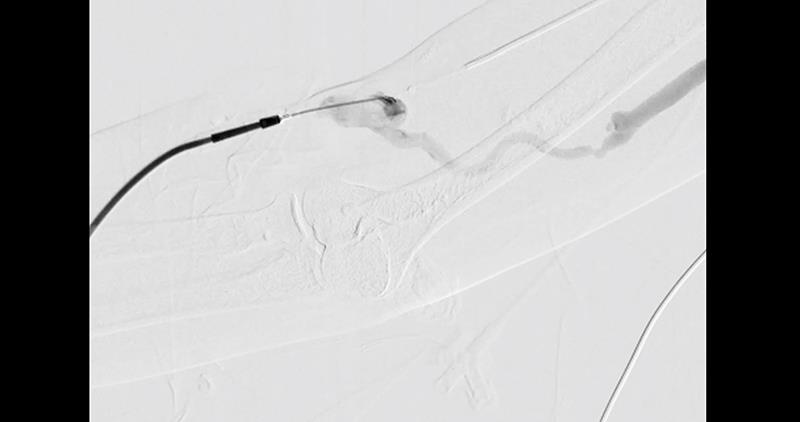

The SEB used in both studies features spherical micro-reservoirs made from a solid solution of biodegradable polymer intermixed with sirolimus, coated onto a standard PTA balloon catheter. This design enables the controlled and sustained release of sirolimus in an "eluting" manner upon drug transfer to the arterial wall. [J Endovasc Ther 2020;27:683-690; JACC Cardiovasc Interv 2024;17:1547-1556]

Of note, the technical success rate was 100 percent, indicating that the SEB used was able to cross and dilate all the lesions, and achieve a residual angiographic stenosis ≤30 percent.